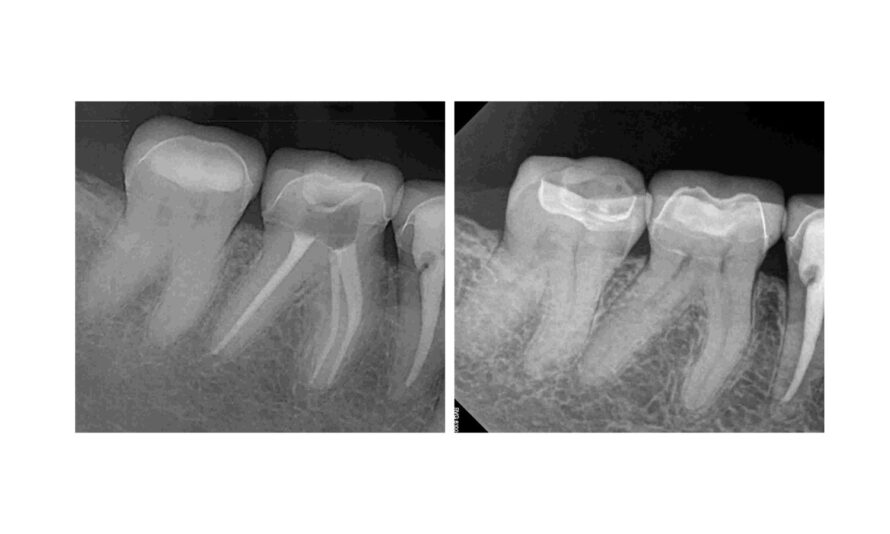

If you’re searching for a root canal in Bellevue, it’s important to understand both the cost and what the procedures entails. Root canals are nonsurgical procedures during which a dentist removes infected pulp and bacteria from inside the tooth. The main goal is to preserve the natural tooth — that avoids extraction.

- Removes infected and damaged pulp from the canal

- Cleans and shapes the canal

- Fills the canal with a special dental material